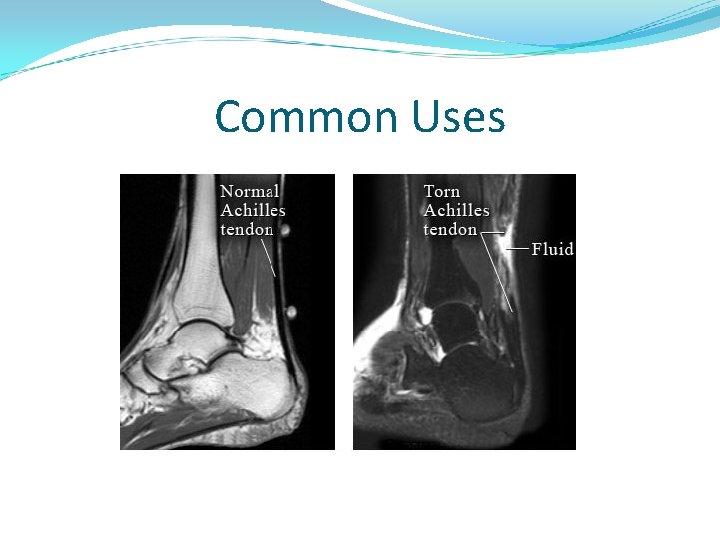

Common Uses Physicians use the MR examination to help diagnose or monitor treatment for conditions such as: Tumors and other cancer related abnormalities. Certain types of heart problems. Blockages or enlargements of blood vessels Diseases of the liver, such as cirrhosis, and that of other abdominal organs. Diseases of the small intestine, colon, and rectum

Common Uses